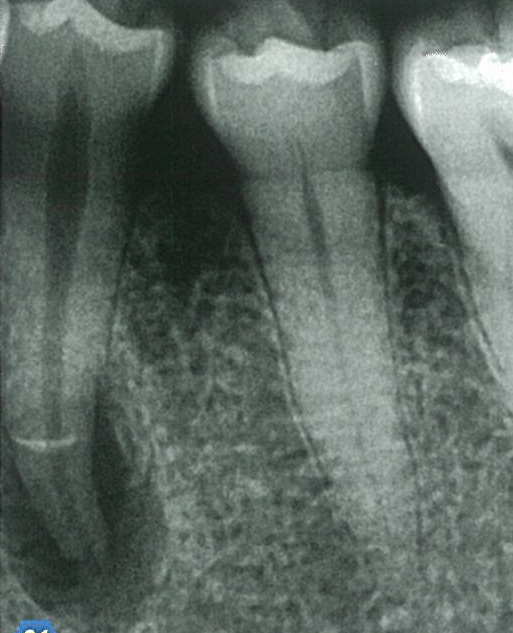

치아가 감염된 지 오래된 경우 방사선 사진에서 치근단 병소가 발견됩니다. 방사선 사진 상 병소의 크기가 작으면 당연히 신경치료를 진행하겠지만, 병소의 크기가 크다면 수술 혹은 발치 가능성까지 생각하게 됩니다. 이럴 때 신경치료라는 방법을 선택하게 된다면 어떤 방식으로 진행해야 할지에 대한 고민이 들기 시작합니다. 이런 경우에 사용할 수 있는 것이 chlorohexidine과 calcium hydroxide입니다.

감염이 오래된 경우 치근단 병소의 크기가 커집니다. 또한 pus가 나오거나, 누공(fistula)이 생기거나, 좋지 않은 냄새가 나곤 합니다. 이 외에도 만성 염증과 급성 염증의 경우 박테리아의 구성이 다르다는 것이 중요합니다. 따라서 오래된 감염 근관을 치료할 때는 기존의 근관 세척 방법에 추가적 단계가 필요합니다.